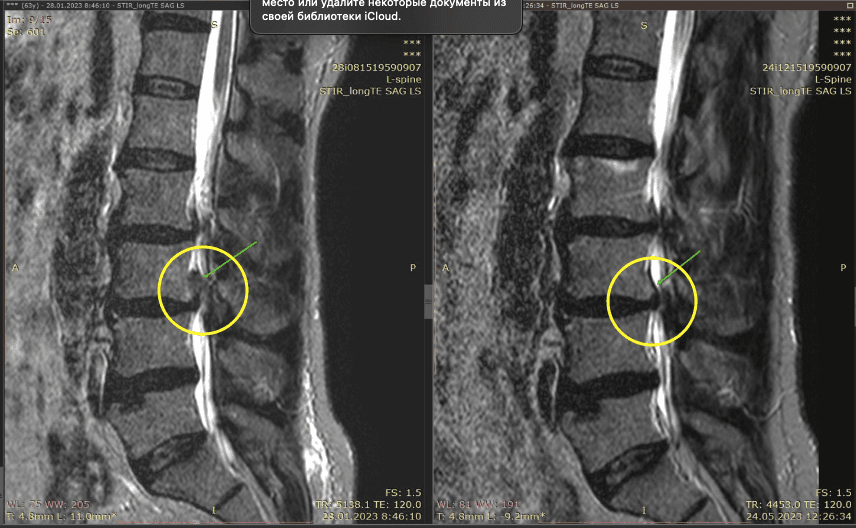

Метод лікування грижі шляхом стимуляції резорбції в Україні був впроваджений у 2020-2021 роках.  Алгоритм оцінки грижі на предмет резорбції, що використовується у клініках – є авторським, розроблений лікарем Боханом А.Ю.